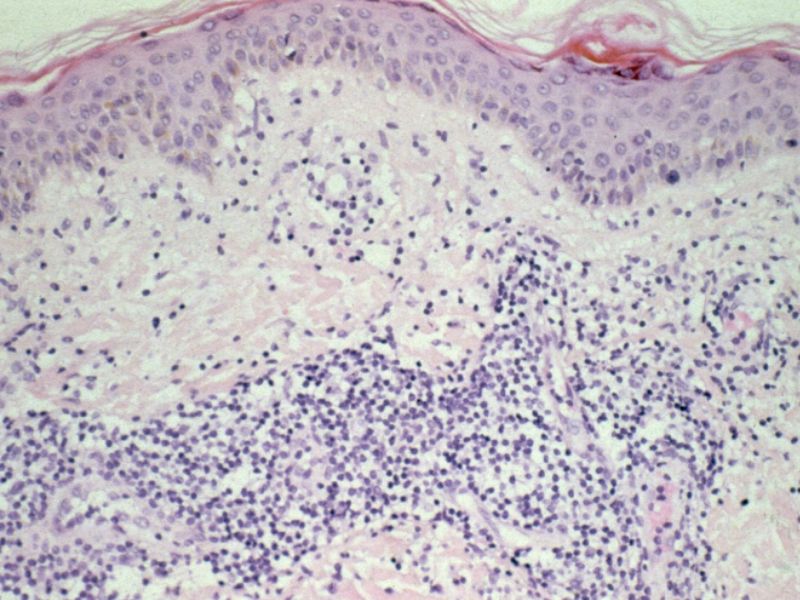

PA:Dicht lymfocytair infiltraat. Immuno-histologisch

is EMAP identiek aan M. Jessner. Mengbeelden zijn ook waargenomen bij één en

dezelfde patiënt. Daarom neemt men aan dat het om dezelfde entiteit gaat. Toch

is het vanwege de bijzondere vorm, het verspringend karakter (M. Jessner laesies

zijn doorgaans meer persistent), en de voorkeurs lokalisatie op de rug (Jessner

lesies bevinden zich vaker in het gelaat) nuttig om deze huidziekte als aparte

entiteit te handhaven.